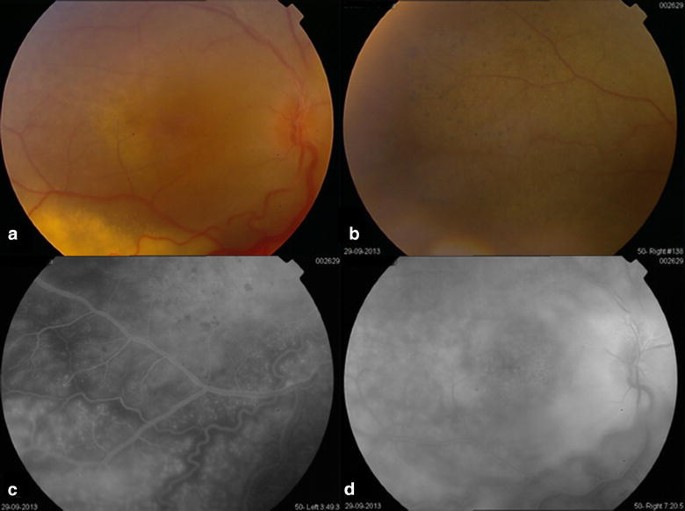

Атрофия зрительного нерва Лебера: Симптомы и лечение